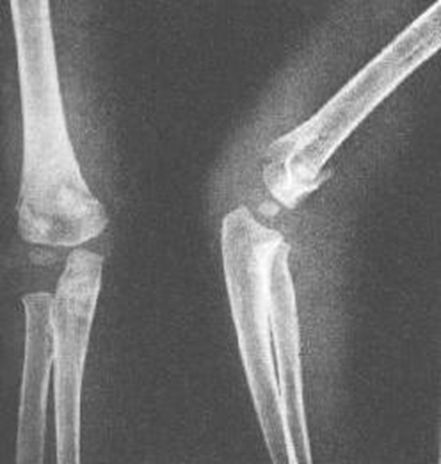

肱骨髁上骨折

肱骨髁间骨折